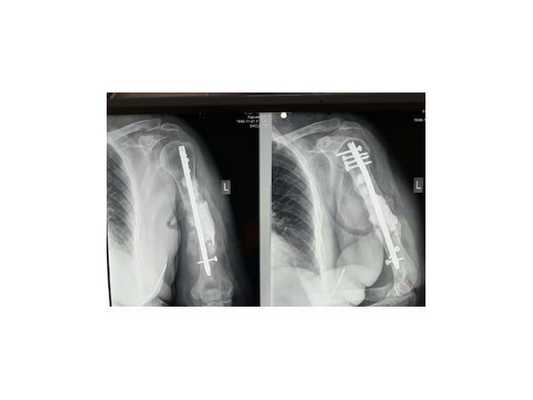

2. Больная В., 47 лет, поступила через 2 года после автотравмы с диагнозом: атрофический ложный сустав правой плечевой кости, перелом фиксатора (рис. 2). Рисунок 2. Рентгенограммы больной В., 47 лет (I), и функция конечности через 2 нед после операции (II). I: а - многооскольчатый перелом правой плечевой кости, б - интрамедуллярный остеосинтез, в - несостоятельность фиксатора через 3 мес, г - реостеосинтез пластиной с угловой стабильностью, д - перелом накостного фиксатора спустя 18 мес, е - реконструкция плечевой кости - накостный остеосинтез метафизарной пластиной с применением ротированного на сосудистой ножке надкостнично-кортикального аутотрансплантата, ж - консолидация ложного сустава через 5 мес; II - функция конечности через 2 нед после операции.